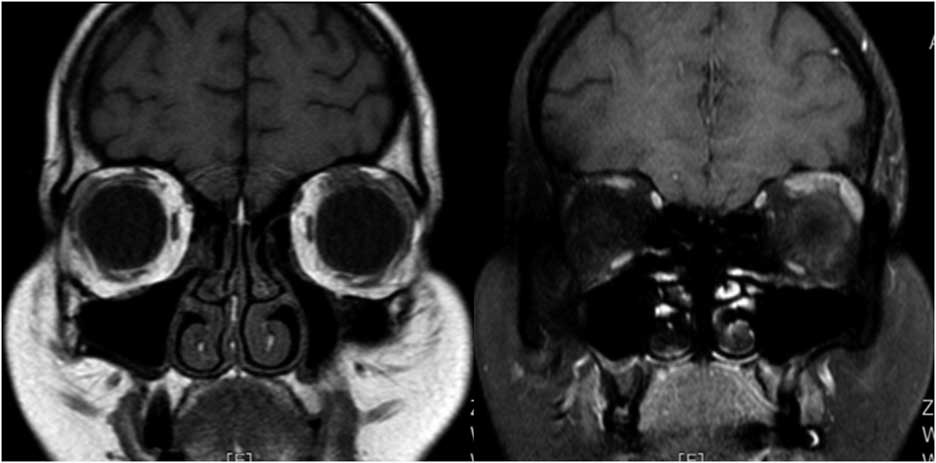

Case 2: A 33-year-old male presented with right conjunctival redness and retrobulbar pain exacerbated by eye movements that had lasted for a month. In the following weeks, he developed diplopia and right-eye ptosis. Neurologic examination demonstrated right-side ptosis and proptosis. In primary gaze, he had right exotropia. Right extraocular movements were totally restricted in elevation, depression, and adduction, and he had mild limitation of abduction (Figure 2a). Pupils reacted normally to light with mild right-eye mydriasis. Orbital MRI showed edema and enhancement of the right lateral rectus muscle partly involving surrounding fat (Figure 2b). CSF examination did not show any abnormalities. Subsequent investigations did not show any abnormalities in CBC, TFT, antithyroid antibodies, ANA, ANCA, IgG4 levels, and viral serology. Brain MRI, intracranial MR angiography, and chest CT were also normal. He received intravenous methylprednisolone (500 mg/day for 5 days) followed by oral prednisolone (1 mg/kg/day), and his symptoms improved slowly over 2 months, and he gained recovery in ocular motility within 5 months, except for diplopia in extreme lateral gaze. After treatment, his MRI showed resolution of edema and enhancement in the right lateral rectus 2 months later (Figure 2c).

Figure 2b Axial MRI scan demonstrating right lateral rectus thickening and contrast enhancement.

Figure 2c Repeat MRI 2 months later shows resolution of edema and enhancement in the right lateral rectus.